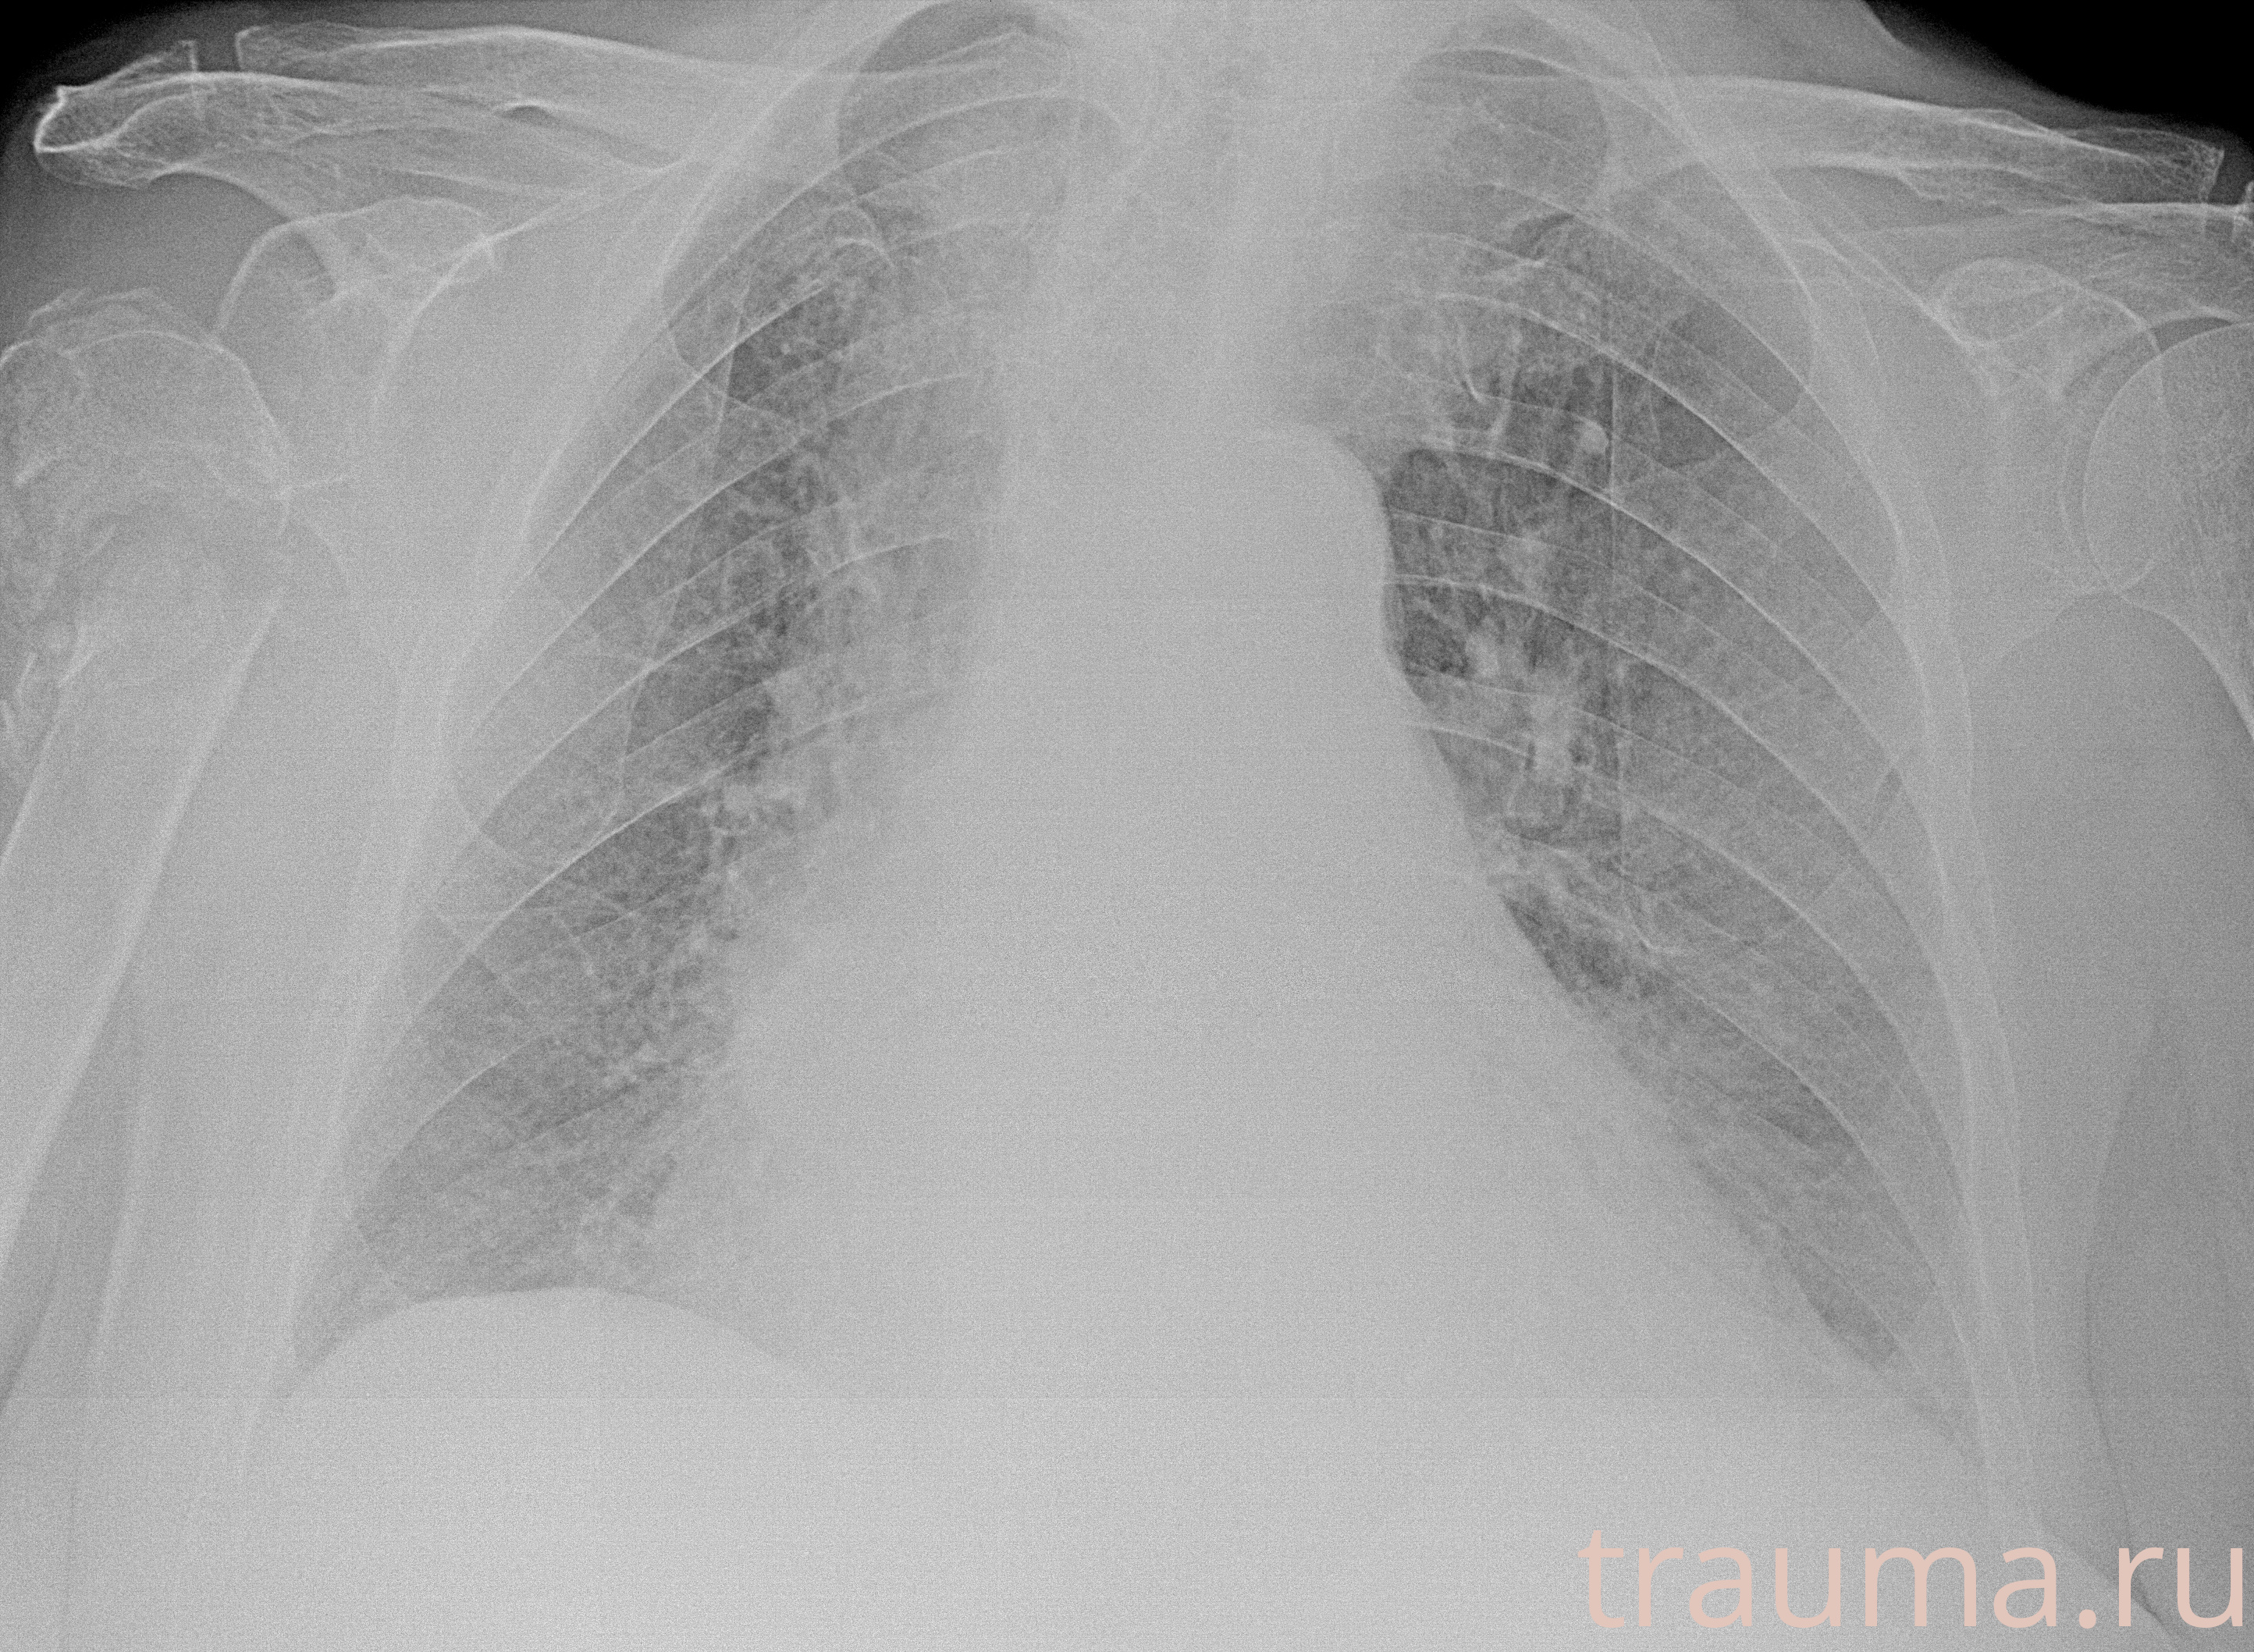

Рентгенограммы

Рентген на дому: по вашему адресу приезжает врач-рентгенолог, травматолог-ортопед с мобильным рентгеновским аппаратом, проводит диагностику травмы или заболевания, делает необходимые рентгенограммы, дает рекомендации по дальнейшему лечению. Получить качественные снимки в домашних условиях возможно благодаря уникальной методике, разработанной МосРентген Центром для института  Склифосовского